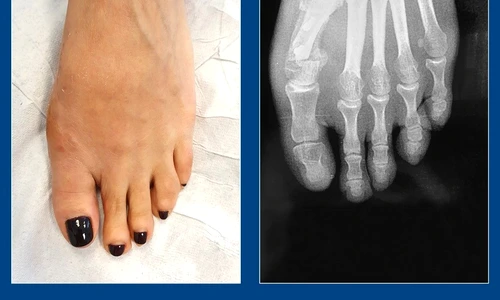

Monturile pot fi corectate doar prin intervenţie chirurgicală